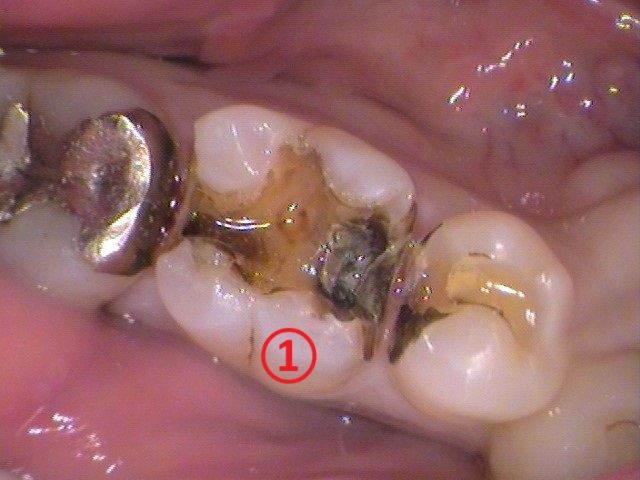

ナンバリングしてあります、①番と、②番の歯を見てみましょう。

①銀歯の中で分かった虫歯

お口の中の状態を見てみると、

①番、②番ともに銀歯が入っています。

レントゲン写真を確認してみると、

銀歯の下に黒く、丸い影が出ているのが分かりますでしょうか?

この記事の最初の方で説明したように、銀歯の下でも虫歯が大きければ虫歯の影を確認できます。

銀歯を削って外してみましょう。

一つ手前の銀歯も外していますが、銀歯を外してみると、なんだか綺麗ではありません。接着剤の残りカスもついているので、削って綺麗にしてい行きます。

そして、虫歯を染色する「う蝕検知液」のお薬を使うと、

銀歯の中で赤く色が染まる虫歯が確認できました。レントゲン写真から想定出来たように、虫歯が大きく広がっています。

手前の歯の中にも虫歯がありました。